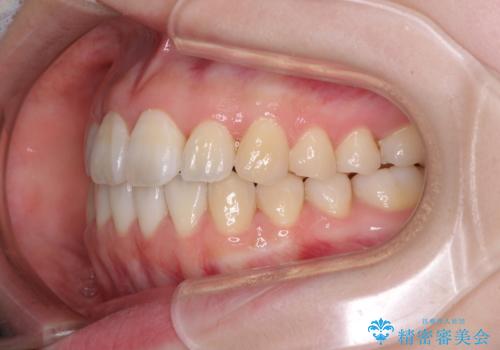

- 前歯の捻れと、ちょっとした出っ張りを気にして来院された患者様です。

歯と歯の間を削る(IPR)ことでデコボコを解消し、インビザラインで整えることとしました。

インビザライン治療特有の奥歯が接触しない時期が続き、当初予定よりも期間がかかりましたが、最終的には安定した咬み合わせと、整った前歯になりました。